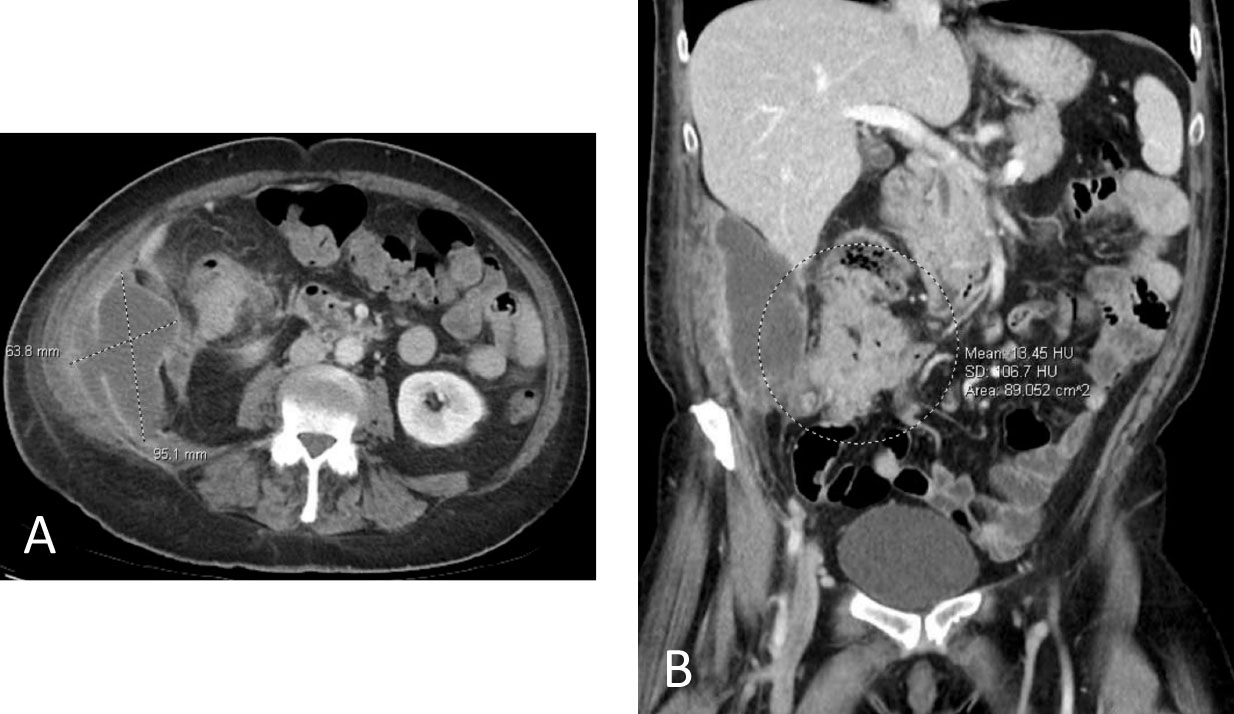

CT (A) axial and (B) coronal views.

A large mass was found in the cecum with involvement of the small bowel.